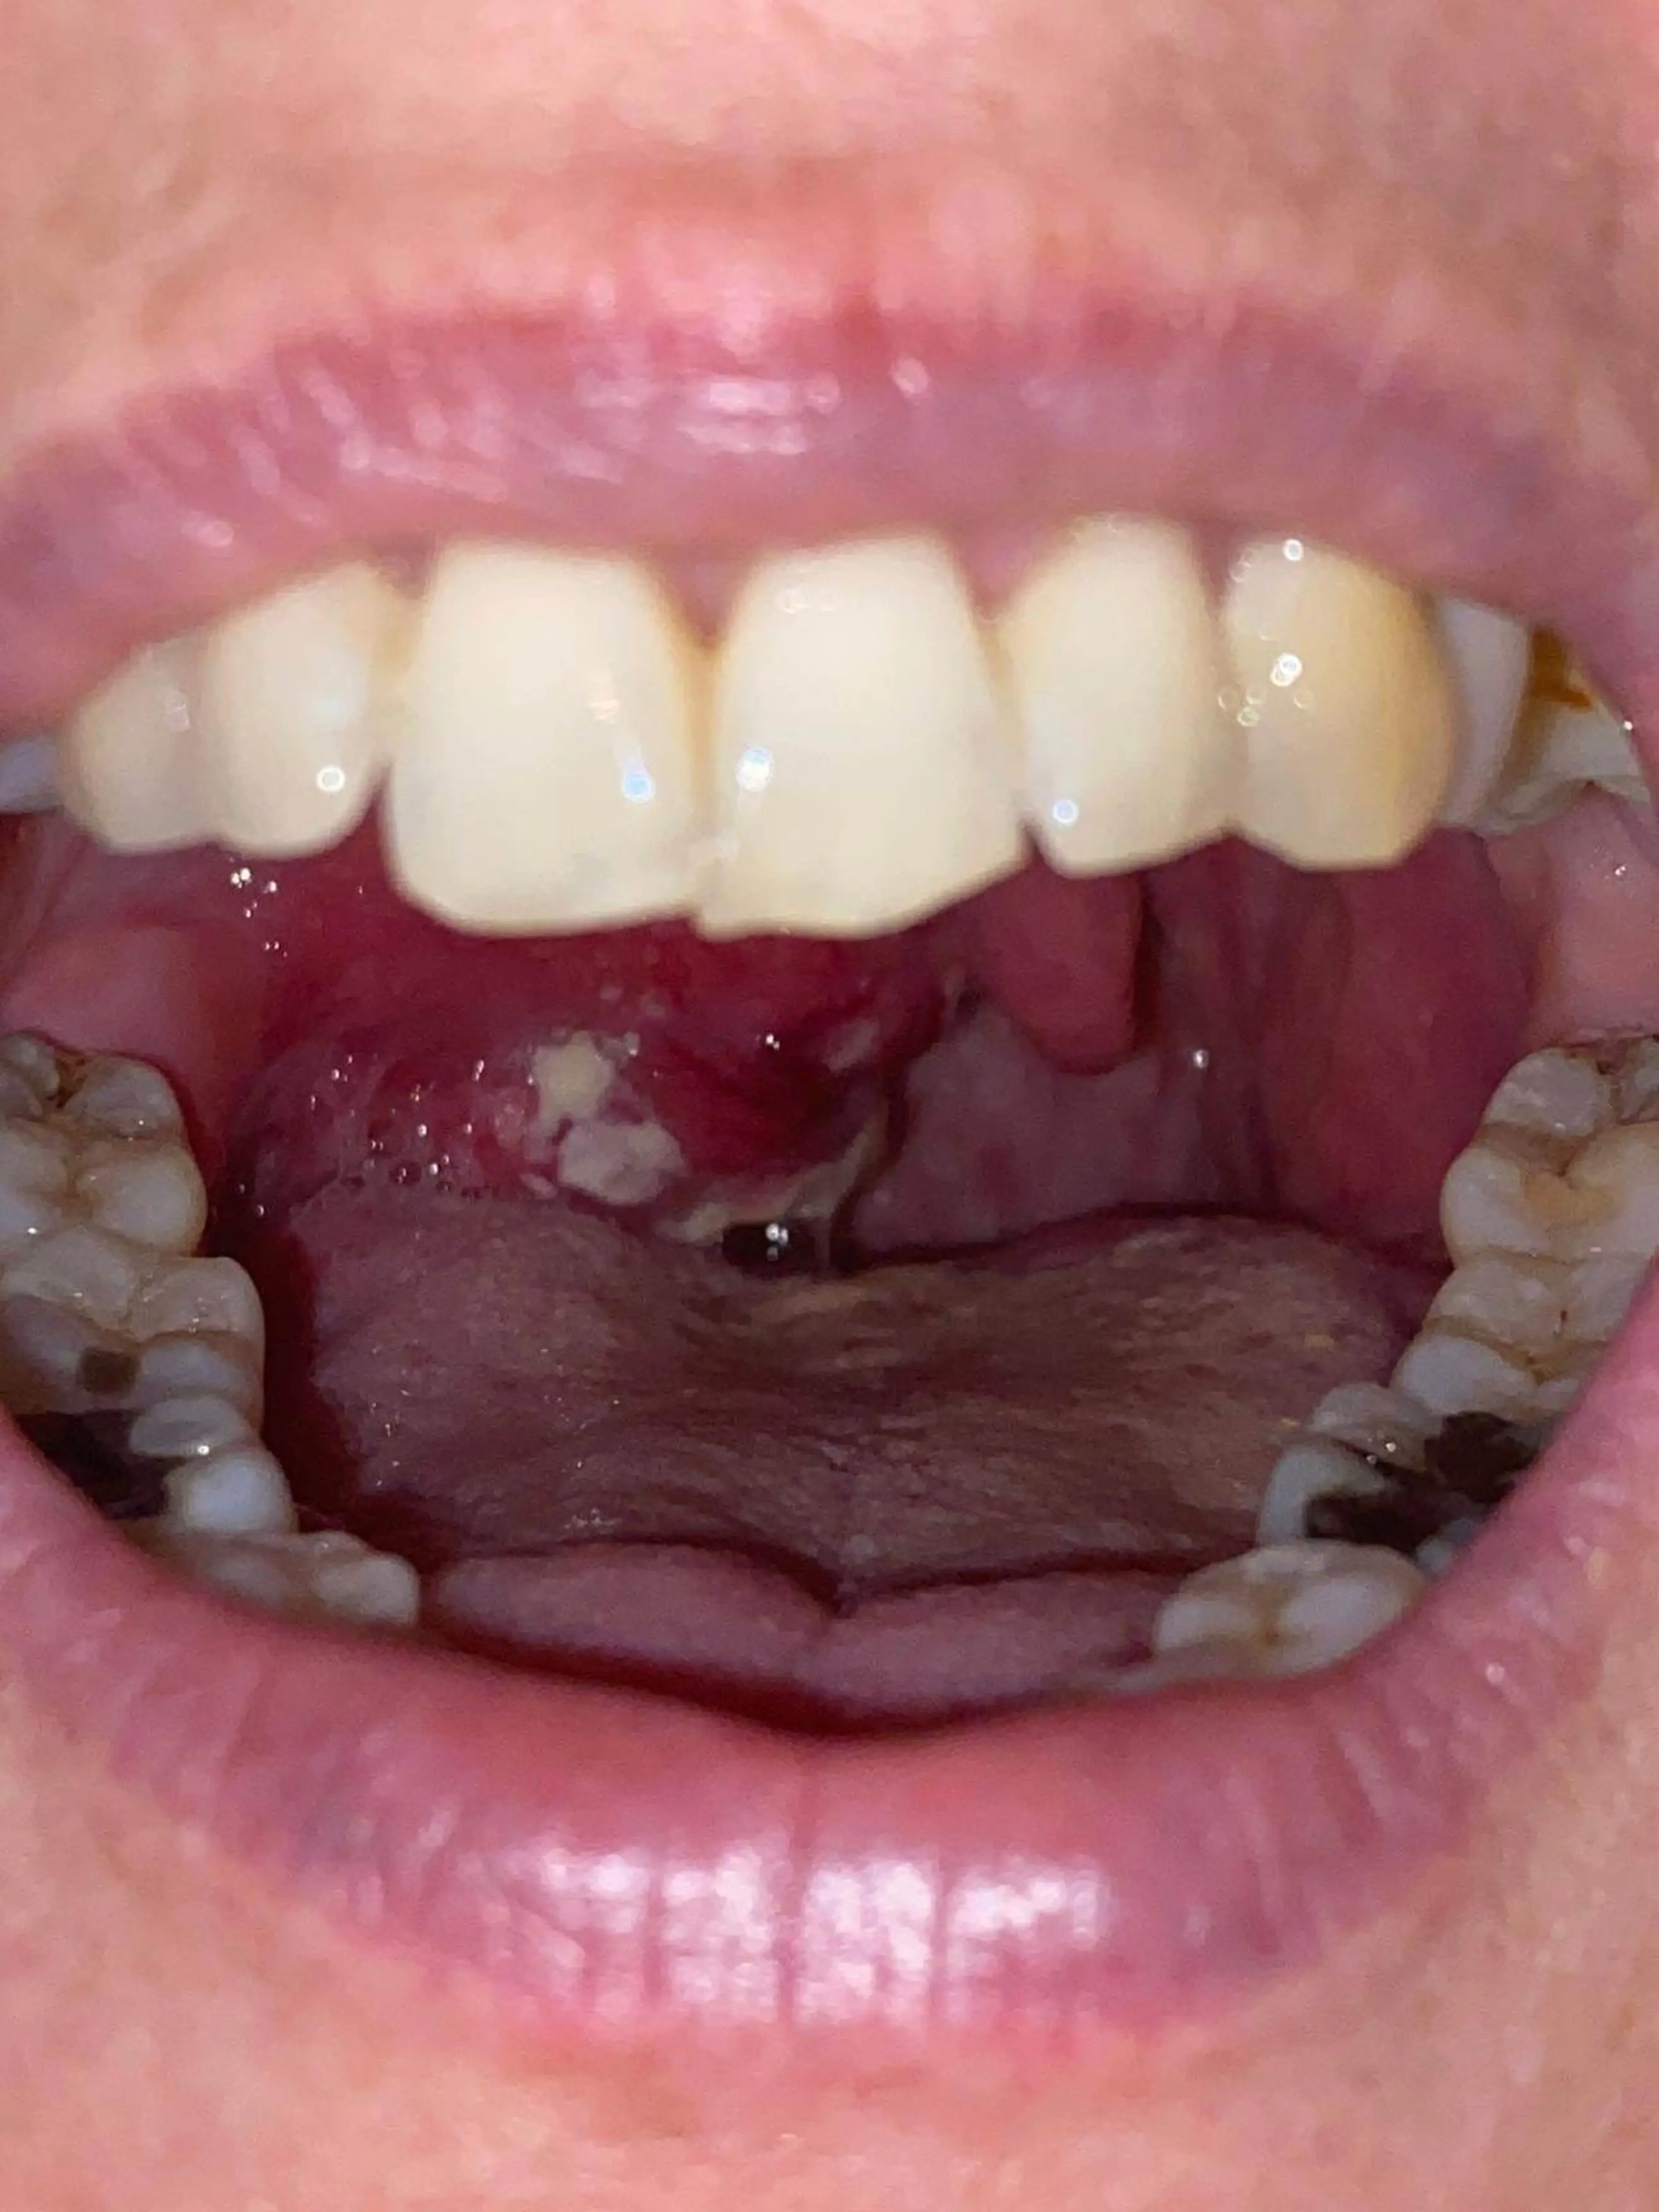

Lisa Gooddy, from Stockport, Greater Manchester, noticed a few white patches on her tonsils back in 2019, and went to her GP to get it checked out.

However, the 51-year-old was told that it was just something called tonsil stones, which are small lumps that form on the tonsils.

"There was a white patch on my tonsil and I've had tonsil stones in the past but unfortunately I wasn't referred at that point as they thought it was tonsil stones."

And in December 2020, the customer support assistant was given the devastating news that she had T2 tonsil cancer.

Lisa was told by the doctor that the disease had also spread to her soft palate and lymph nodes in her neck.